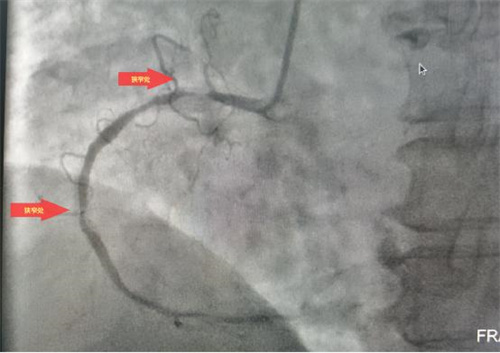

術(shù)前

據(jù)了解,此次順利完成經(jīng)皮冠狀動脈內(nèi)支架植入術(shù)的患者共有4位,其中一名68歲老年女性患者,因胸悶氣促6余年,活動后明顯加重入院治療。經(jīng)冠脈造影檢查,發(fā)現(xiàn)左前降支次全閉塞、右冠99%重度狹窄,三支血管重度病變,情況危急。經(jīng)病情評估后,與患者家屬溝通,決定立即對右冠實施冠狀動脈球囊擴張加支架植入術(shù)。在上級專家的指導下,心病科團隊成功擴張了狹窄血管、植入支架,手術(shù)順利,患者術(shù)后安返病房,為患者后續(xù)治療創(chuàng)造了有力條件。